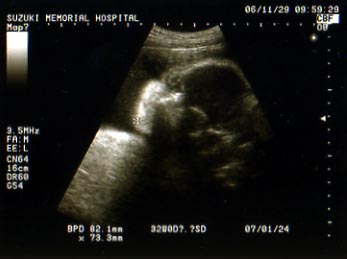

今日は顔がはっきり見えるエコー写真もらいました。

ちょっと目が不気味なんですけどね。

…ちなみに旦那さんに見せたら「??」だったので

一応解説をいれると

こんな感じです。